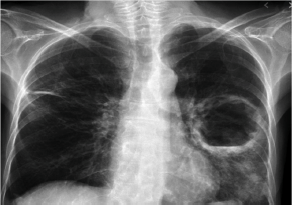

Homem de 40 anos, em situação de rua e etilista, é trazido por seus companheiros ao hospital. O paciente apresenta febre e perda de peso há 4 semanas, acompanhado de tosse com escarro purulento. Ao exame físico, emagrecido, em regular estado geral, com sinais vitais estáveis. Realiza RX tórax:

Sobre a patologia que apresenta, assinale a afirmativa correta.